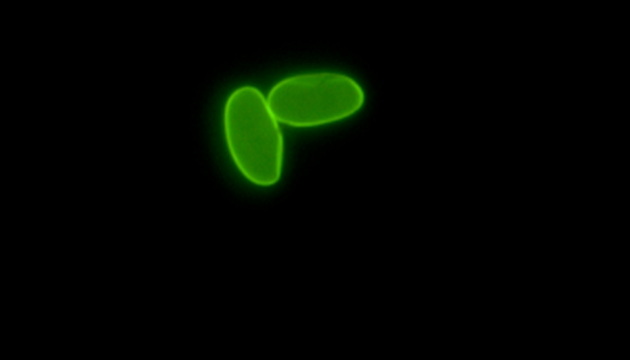

两虫指的是贾第鞭毛虫(Giardia)和隐孢子虫(Cryptosporidium),它们是主要的水源性原生动物寄生虫,通过被污染的饮用水或食物感染人类,引起腹泻等疾病,且大多数抗生素对其无效,严重威胁水质安全和人类健康。

显微成像在检测两虫中扮演关键角色,通过免疫荧光法结合专业的荧光显微镜,能高效区分并识别水体中的贾第鞭毛虫和隐孢子虫,确保饮用水安全。这种方法提高了检测的准确性和效率。

为解决显微成像在两虫检测中的难题,可采用高性价比的研究级LED荧光显微镜MF43-N,其成像荧光信号强,操作简单,检出率高,有效提升了检测效率和实用性,是水质监测单位理想的解决方案。